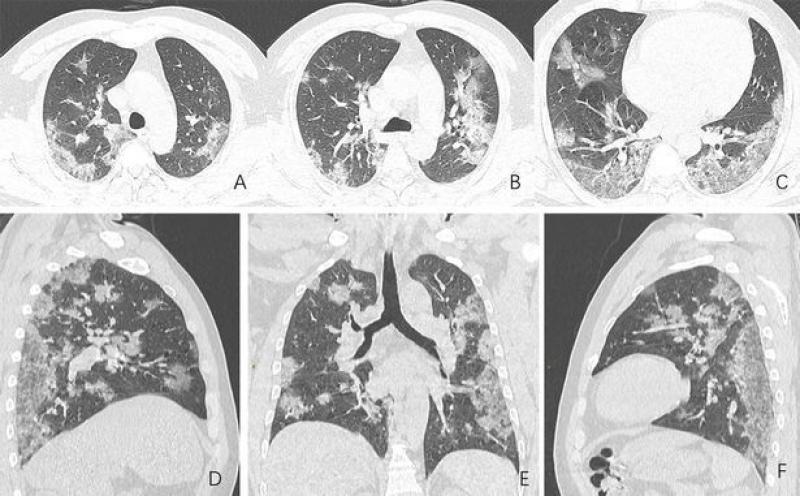

De internationale vereniging van radiologen RSNA heeft nu röntgenfoto's gedeeld van de longen van de bewuste man. Daarop zijn duidelijk witte vlekken te zien die steeds groter worden (zie foto van A tot en met F).

Ontstekingsvloeistof

Dat zijn zogenaamde ground-glass opacities (GGO's) waarbij de longblaasjes zwellen en vollopen met ontstekingsvloeistof. Deze symptomen zien we ook terug bij mensen die lijden aan het SARS-virus en het Middle East respiratory syndroom (MERS).